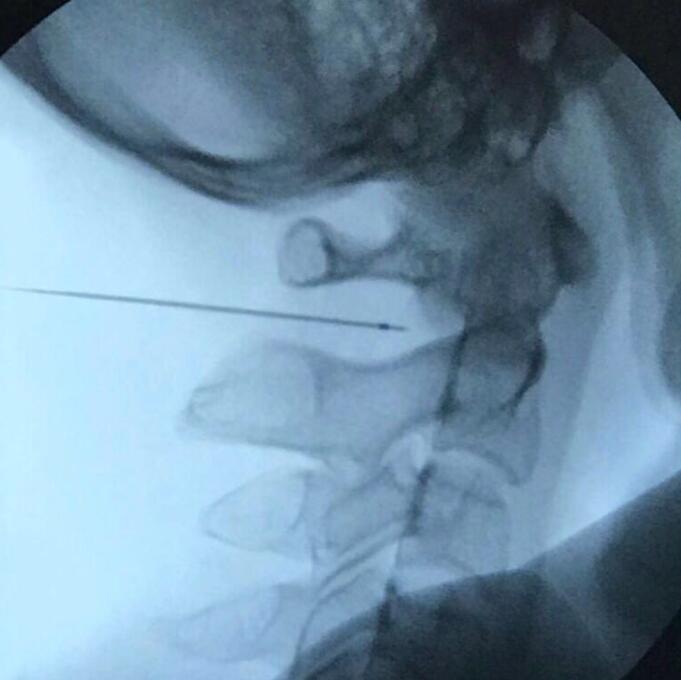

穿刺到位後的X線側位片

據醫生介紹,手術是先用X線透視,確定目標,然後穿刺到靶點神經或神經節,進行電生理測試,包括運動測試和感覺測試。這兩個測試會誘發出肌肉跳動和麻脹感,如果肌肉跳動和麻脹感的位置與術前的疼痛部位一致,就表明穿刺是準確的。最後,進行脈衝射頻,就是用42°-50°的溫度對神經功能進行調節,這必須依靠多年的豐富經驗,才能做得恰到好處。